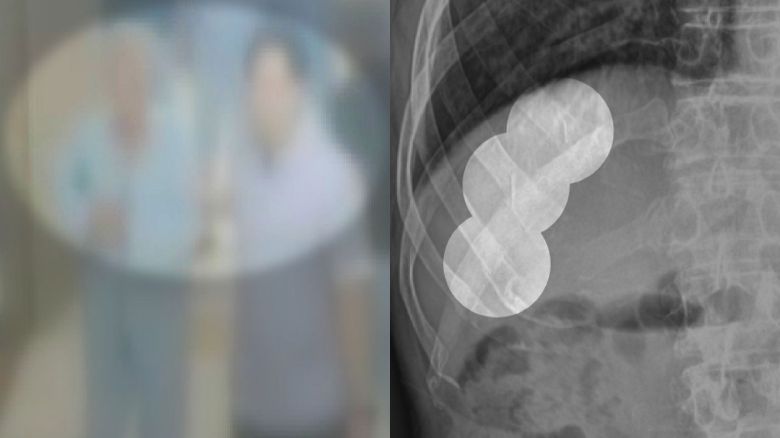

제보자 아버지는 당뇨 등으로 전남 목포의 한 병원에서 약 8년간 치료를 받아오던 중 지난해 11월 보호사에게 폭행당해, 갈비뼈가 골절됐습니다.